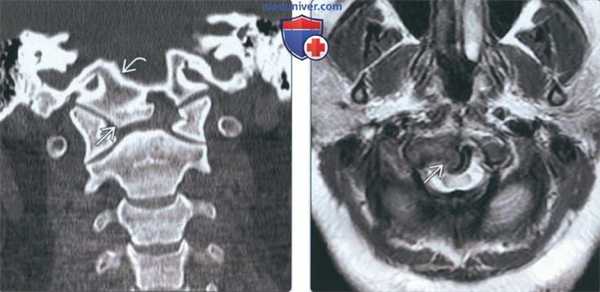

(Слева) На рентгенограмме шейного отдела позвоночника в боковой проекции (нейтральное положение) визуализируется дистопическая зубовидная кость, слившаяся со скатом. Также определяется гипоплазия зубовидного отростка.

(Справа) На сагиттальной КТ в костном окне визуализируется зубовидная кость, слившаяся в единое целое со скатом. Определяется ремоделирование передней дуги С1 и зубовидной кости наряду с гипоплазией задней дуги С1, находящейся в позвоночном канале сразу же под большим затылочным отверстием.

(Слева) На корональной КТ в коаном окне определяется слияние дистопической зубовидной кости со скатом (эксцентрически смещенным вправо).

(Справа) На аксиальной MPT (Т2) определяется патологический сигнал высокой интенсивности в шейном отделе спинного мозга на уровне С1, отражающий его повреждение, обусловленное атланто-аксиальной нестабильностью и легкой гипоплазией С1 в сочетании с эксцентрической птичьей костью.